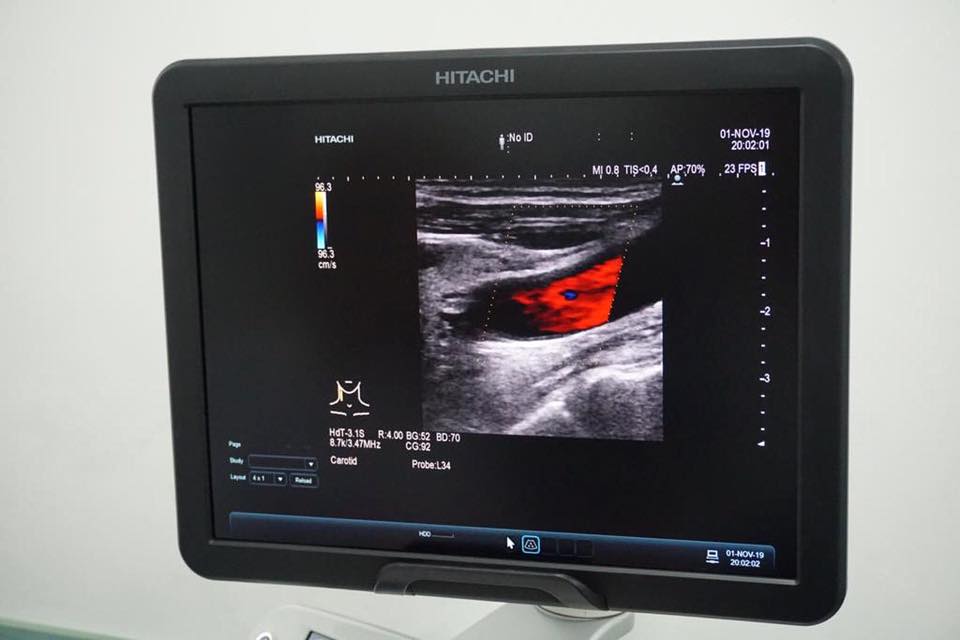

Primele două au ajuns marți și sunt esențiale atunci când vine vorba de o afecțiune des întâlnită: Accident Vascular Cerebral – AVC. Este vorba de aparatul de ultrasonografie Doppler cu sonde pentru examenul extracranian al arterelor cervicocerebrale și un aparat sistem Doppler transcranian pentru examenul transcranian al arterelor cerebrale.

„Aceste noi achiziții permit identificarea cauzei ???, evaluarea corespunzătoare a pacienților, dar și tratamentul țintit pentru a preveni reapariția bolii. De asemenea, pot fi evaluate persoane care suferă de o boală care crește riscul apariției ???, dar și persoanele care manifestă simptome precum tinitus, tulburări de vedere, vertij sau amorțeli ale membrelor. Cât despre programul național în care a fost inclus și spitalul nostru, coordonat de d-na Dr. Oana Toma, medic specialist neurolog, acesta își dovedește eficiența, mulți pacienți care au beneficiat de tratament intervențional în caz de ??? fiind recuperați.”, a explicat dr. Gabriela Deak, director medical la Spitalul Judeţean.

„De data aceasta este vorba despre o investiție în sănătate de 749.516 lei (156.845 euro), iar dotarea Spitalului nostru va continua. Județul nostru trebuie, merită și poate să aibă un Spital unde profesioniștii, aparatura performantă, calitatea și continua dezvoltare să facă echipă, pentru toți cei ce au nevoie”, a scris președintele CJ BN, Radu Moldovan, pe Facebook.